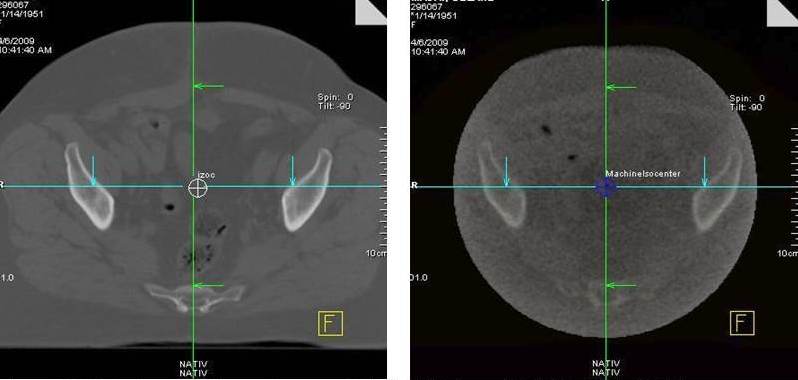

Treatment planning CT image with isocentre (left side) and verification MV-CBCT image with isocentre of the treatment machine (right side) for pelvic irradiation.